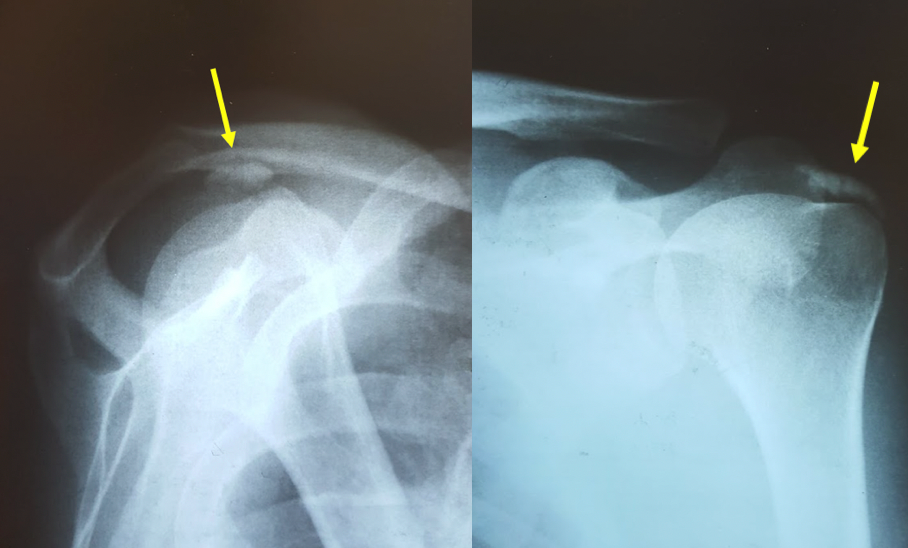

Diagnóstico: pode ser confirmado com o RX, ultra-sonografia ou ressonância magnética.